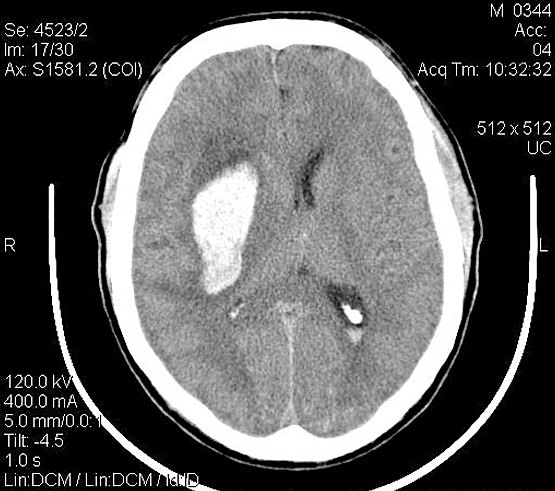

Порэнцефалия

Порэнцефалия на МРТ

Порэнцефалия - наличие в головном мозгу содержащих жидкость полостей. Последние могут быть как единичными, так и множественными, чаще располагаются симметрично и связаны с желудочковой системой. Основание пузыря обычно доходит до поверхности больших полушарий.

Извилины мозга, окружающие полость, направляются к ней радиально, в них наблюдается ряд дегенеративных изменений (уменьшение количества и величины нервных клеток, неправильное их расположение).